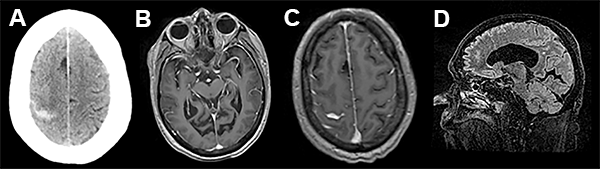

A las 72 hs de la segunda intervención comienza con cefaleas intensas, náuseas, trastorno del sensorio por lo cual se realiza nueva internación, evidenciando mediante TAC sangrado subaracnoideo (fig. 2).

Figura 2

En el presente trabajo, los autores reportan un evento hemorrágico cerebral como complicación de una fistula de líquido cefalorraquídeo (LCR) asociada a una cirugía espinal lumbar mini invasiva. Dicho evento se desencadenó 72 hs luego de la reparación de la fístula de LCR, presentándose como una hemorragia subaracnoidea de la convexidad cerebral. Esta complicación ha sido descrita por numerosos grupos,1-5 siendo la localización mas frecuente el cerebelo. Si bien las imágenes de tomografía y resonancia magnética nuclear evidencian la presencia de hemorragia subaracnoidea en el surco central derecho, llama la atención la asimetría de surcos con hipodensidad en el área premotora derecha, similar a los hallazgos asociados con una trombosis venosa. Más aún, considerando que el paciente tiene antecedentes de trombosis venosa profunda e ingresa a las 72 horas por trastornos del sensorio (difícilmente explicables sólo por una hemorragia subaracnoidea de la convexidad), no podemos descartar con las imágenes brindadas la presencia de trombosis venosa, complicación también descripta como consecuencia de una perdida de LCR.6-9 Si bien ambas complicaciones son de muy baja ocurrencia, es importante reconocer su existencia a la hora de evaluar un postoperatorio de cirugía espinal complicado con fistula de LCR en pacientes añosos.